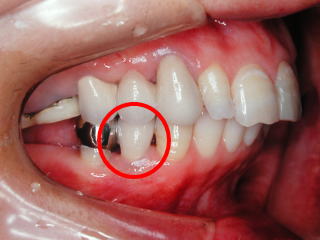

奥歯のところに親知らずを

移植して、接着剤で固定

したところ

抜いた親知らず